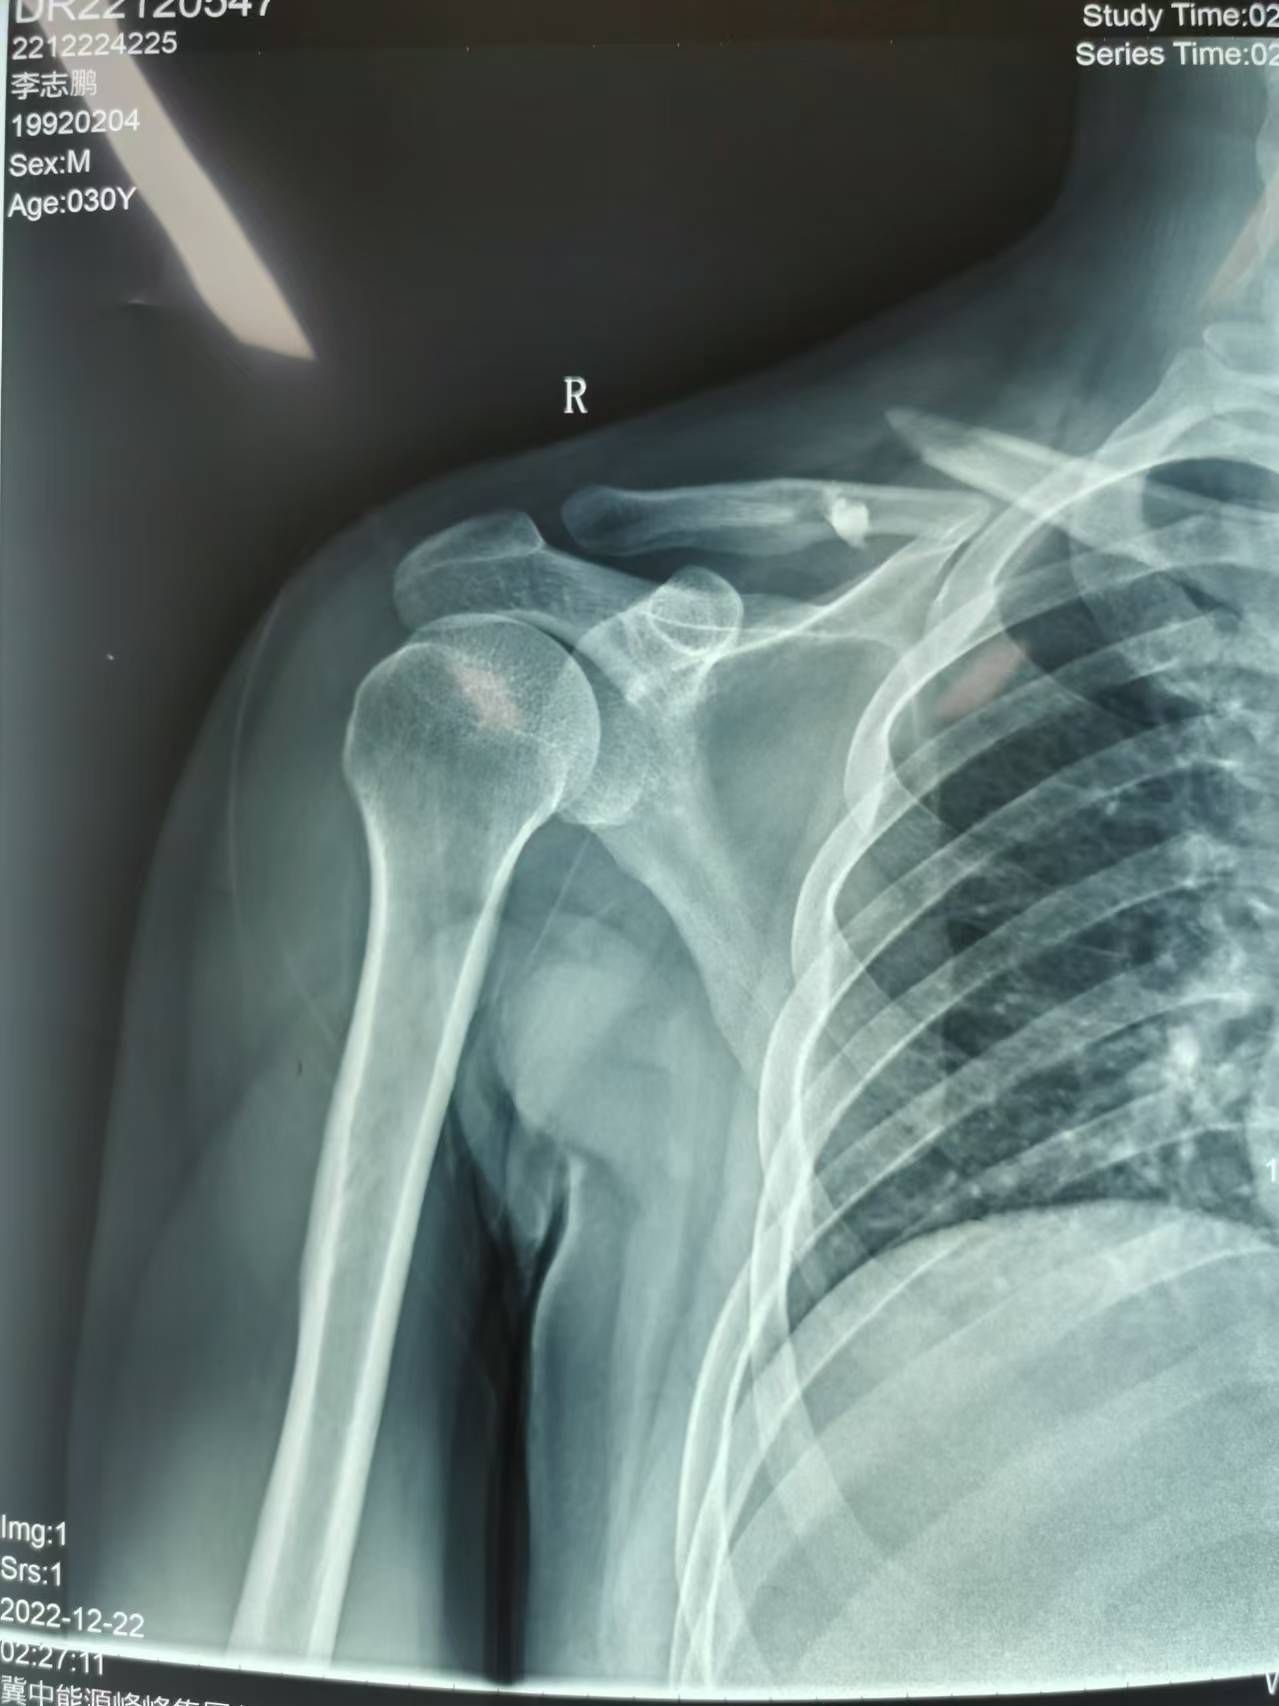

首页 > 张恒云工作室 > 影像资料 六